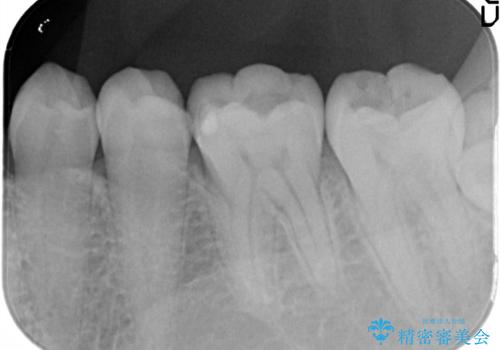

- 金属の詰め物がはずれてしまったので、精度の良いセラミックをいれたいのとのこと来院されました。

セラミックインレーにて治療することとなりました。

拡大鏡を使用して精度の高いインレーを装着しました。